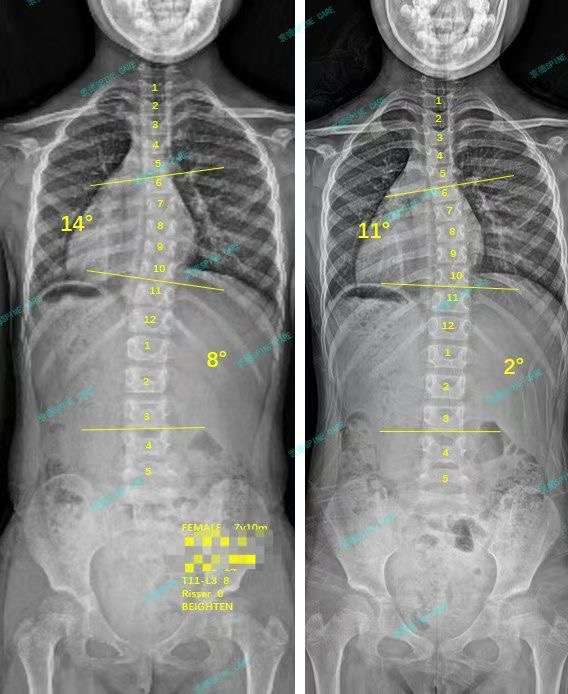

我是淼淼,7岁女孩训练3个月后胸弯降至11度,躯干进入中线~

案例主人:淼淼 发现侧弯年龄:7岁 侧弯情况:Cobb角度14度

练了三个月之后,爸爸妈妈带我再次拍了x片,我的胸弯从14度降到11度,腰弯从8度降到2度,身体也看起来正了很多,我和爸爸妈妈都很开心!谢谢杨博士,谢谢康复师老师们!

After practicing for three months, my parents took me to take x-ray again. My chest bend dropped from 14 degrees to 11 degrees, and my waist bend dropped from 8 degrees to 2 degrees. My body also looked much more upright. My parents and I are very happy! Thank you Dr. Yang, thank you to the rehabilitation therapists!